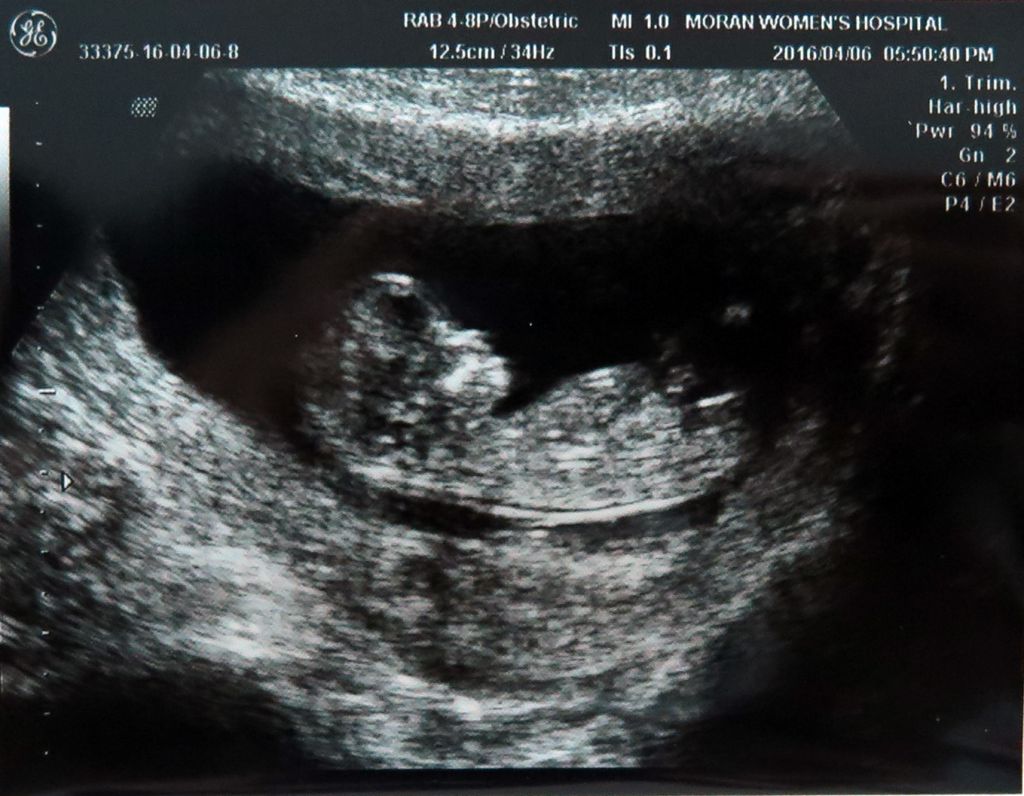

정말 신묘막측이 실감나네요.

우리 별이,,,,

건강하게 자라줘서 고맙고.

한울아! 정말 수고많다.

어제,오늘 너무 바쁜 탓에 피곤하지만 퇴근 후 우리

별이 소식에 하루의 피곤이 싹 가시는구나.

너무너무신기하고 감동이다 ㅎㅎ

노래도 너무 잘 어울리네

별이가 건강하다니 감사하고..

별이엄마는 어서 입덧이 끝나고 마음껏

먹어야 될거같고..

별이아빠는 별이랑 만나기전에 몸매관리

좀해야 할듯 하네요 ㅋㅋ

암튼 너무 너무 감사하다 \(^o^)/

별이 모습 보니 신기하고 반가워 ㅋㅋ

건강하게 잘 있어줘 고마워~~^^